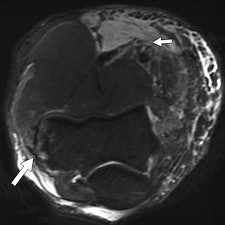

A total of 1,711 radiological investigations were performed at the main Olympic Village polyclinic, of which nearly 50% were MRI exams. Of these investigations, 36 were performed on 30 elbows in 28 athletes, including 26 MRI exams, nine ultrasound scans, and one CT scan. Two athletes underwent MRI of both elbows. Two examinations were of poor quality because of metal artifacts and patient movement. Of the MRI exams, 22 were abnormal, showing at least one pathologic abnormality. Eight of the nine ultrasound scans were abnormal and the lone CT exam confirmed an avulsion fracture, as suspected on MRI.

"Tears of the common flexor and extensor tendons occurred in combination with ligamentous injuries. This occurs because common flexors and extensors act as secondary stabilizers of the elbow joint and are injured when the primary stabilizers fail. Once again, these injuries occurred primarily in combat sports, weightlifting, and overhead-throwing athletes," stated Bethapudi, who was responsible for data collection and analysis at the 2012 Olympics and has received funding from GE Healthcare, a sponsor at the games.

Significant ligament and tendon injuries to the elbow can occur often in nonthrowing athletes, and most of the elbow injuries seen in these athletes were isolated high-grade ulnar collateral ligament (UCL) injuries, although combinations of medial and lateral ligament injuries can occur, the authors concluded. Ulnar attachment tears were the next most common injuries, followed by midsubstance tears of the UCL. This trend differs from the existing literature, which suggests that midsubstance tears are the most common type of UCL injuries, they wrote.